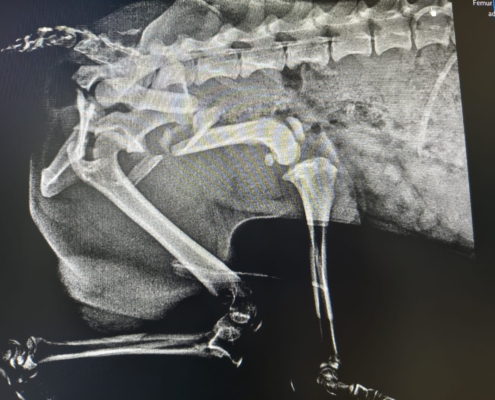

leider war sein Name durch den Umstand entstanden, dass er verletzt (vermutlich durch einen Unfall) auf der Straße gefunden wurde….

Wie lange er schon mit dieser Verletzung unterwegs war…. wir wissen es nicht… auch über sein bisheriges Leben können wir nichts sagen…

Er hat die OP gut überstanden und darf sich noch ein bisschen in der Tierarztpraxis erholen… doch dann braucht er einen sicheren Platz um wieder vollkommen zu genesen…. Leider ist es fast unmöglich vor Ort eine Pflegestelle zu finden… 🙁 und die Finderin, die sich aktuell um ihn kümmert, verlässt im März Rumänien…